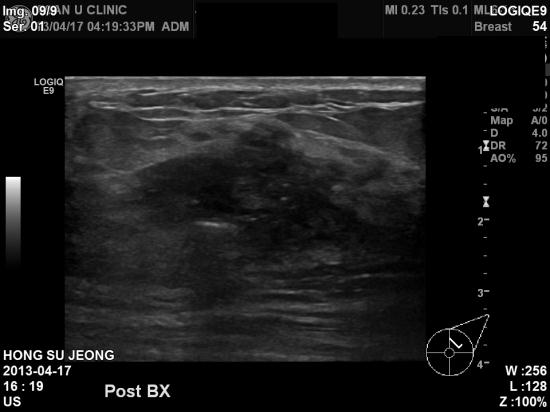

상기환자 우측 유방 멍우리 및 뻐근한 증상으로 내원 하신, 61세 여성분 이십니다.

촉진상 우측 유방 유두 쪽에 크게 만져지 1.5cm정도로 만져지는 혹있어,

초음파 및 조직검사 시행하였으며 검사결과상 유방암으로 진단되었습니다.